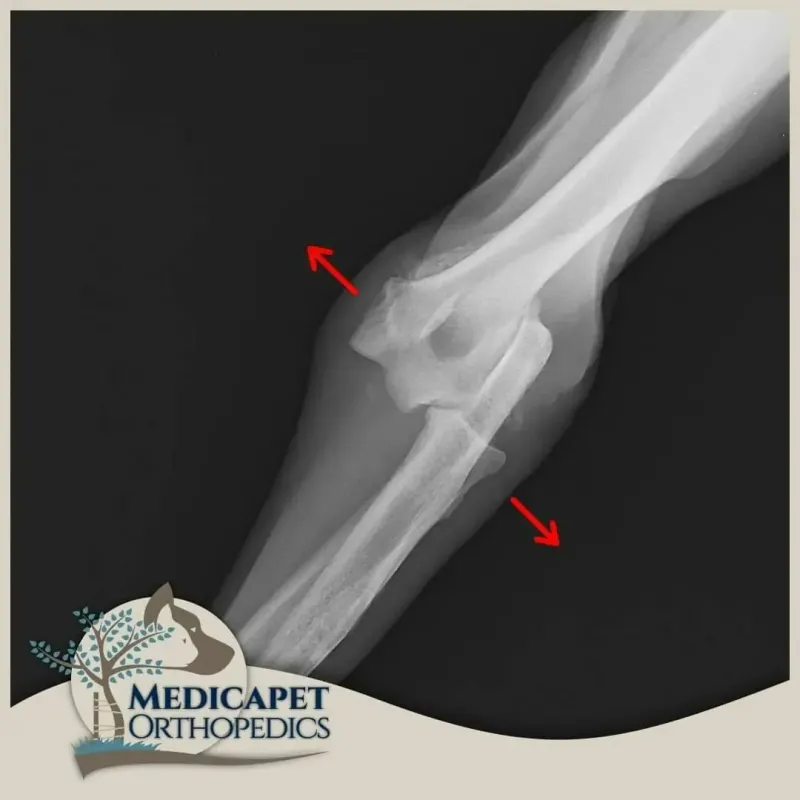

Dirsek çıkığı, genellikle ulnanın eklem içindeki pozisyonundan ayrıldığında meydana gelir. Bu, doğuştan gelen bir durum veya travma sonucu olabilir.

Teşhis, dirsek ekleminin fiziksel muayenesi ve palpasyonu yoluyla yapılır. Travmatik çıkık oluştuğunda hastalar genellikle ilgili bacak üzerine ağırlık vermek istemezler ve sıklıkla bacağı vücuttan uzakta ve kısmen fleksiyonda tutarlar. Fizik muayenede ağrılı bir eklem bölgesi ve anatomik pozisyonda bozukluk görülür. Çıkığı doğrulamak için radyografi kullanırız.

Dirseği saran bağlar ve eklem kapsülünün ağır hasarlı olmadığı durumlarda ameliyatsız kapalı redüksiyon yoluna gidebiliyoruz. Bu tip bir tedavi kısa vadeli etkin takip gerektirir. Dirseğin tekrar çıkması halinde muhtemelen cerrahi tedaviye karar verilecektir. Bağ hasarının yüksek olduğu durumlarda dirsek çıkığının tedavisi açık ameliyat ile yapılır ve hasar gören bağları taklit eden tel, vida ve sentetik bağlardan faydalanırız. Cerrahınız dirsek çıkığının şekline

göre, tedavi seçeneklerini hastanın maksimum faydasına göre değerlendirecektir.